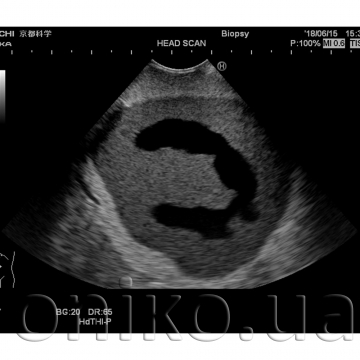

Ultrasound Neonatal Head Phantom (Abnormal type)

World’s First Ultrasound Neonatal Head Phantom with Hydrocephalus

This head phantom is designed to demonstrate abnormal anatomy, such as Hydrocephalus; the shape of the skull is altered due to intracranial pressure.

• Hypertrophied lateral ventricle